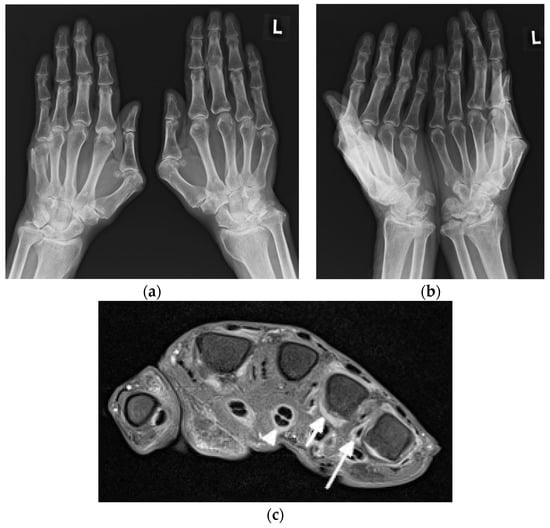

Figure 4.

A 64-year-old female with SLE diagnosed in 1980 with Jaccoud’s arthropathy for hands and feet. (a) Posterior–anterior and (b) oblique radiographs of the hands show bone demineralization; soft tissue swelling at the wrists; periarticular calcifications; malalignment at the distal radioulnar, radiocarpal, and midcarpal joints; dislocation of the 1st carpometacarpal and subluxation of the 1st metacarpophalangeal joints; and joint space narrowing with cyst-like and erosive/destructive changes consistent with rhupus syndrome. Note the reversible contractures at the proximal interphalangeal joints, apparent in (b) and resolved or less apparent in (a). (c) Anterior–posterior standing radiograph of the bilateral feet and (d) lateral standing radiograph of the left foot show bone demineralization, bilateral hallux valgus deformities, and bilateral 2nd and 3rd hammer toes, as well as a right foot with moderate lateral subluxation.